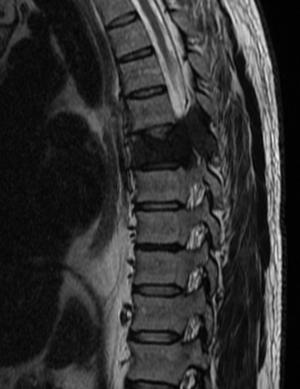

МРТ позвоночника с метастазами: диагностика и лечение